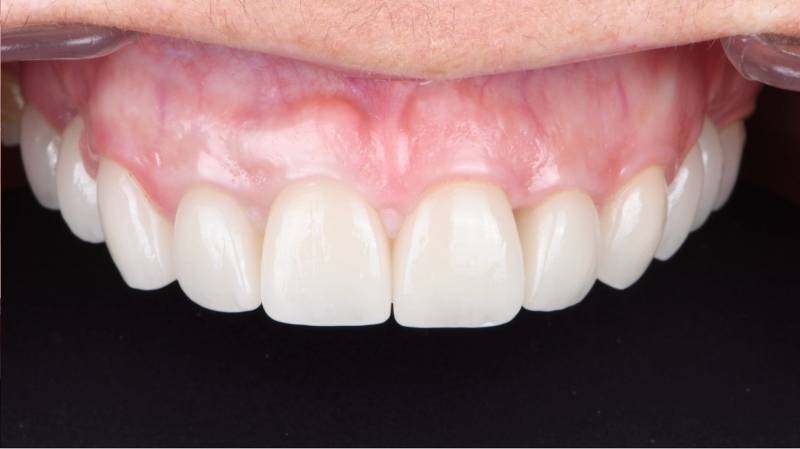

Couronne implantaire en zircone vissée sur l'implant dentaire.

Couronne dentaire vissée sur implant permettant de remplacer une dent absente à Marseille

Mise en place d'une prothèse (couronne ou bridge) sur implant dentaire à Marseille – Réalisation par des chirurgiens-dentistes spécialisés

L'implant dentaire est assimilable à une racine artificielle fixée dans l'os alvéolaire pour remplacer une dent manquante. Il s'agit de la partie immergée de la dent, celle qu'on ne voit pas. La p...

Avant/ Après la pose d'implants dentaires à Marseille

Implants Dentaires : avant/après par des spécialistes de l'implantologie à Marseille 13009

Les Cas Avant/Après d'Implants par les Drs Sebban et Vartanyan, spécialistes à Marseille   Les implants dentaires sont souvent considérés comme une...